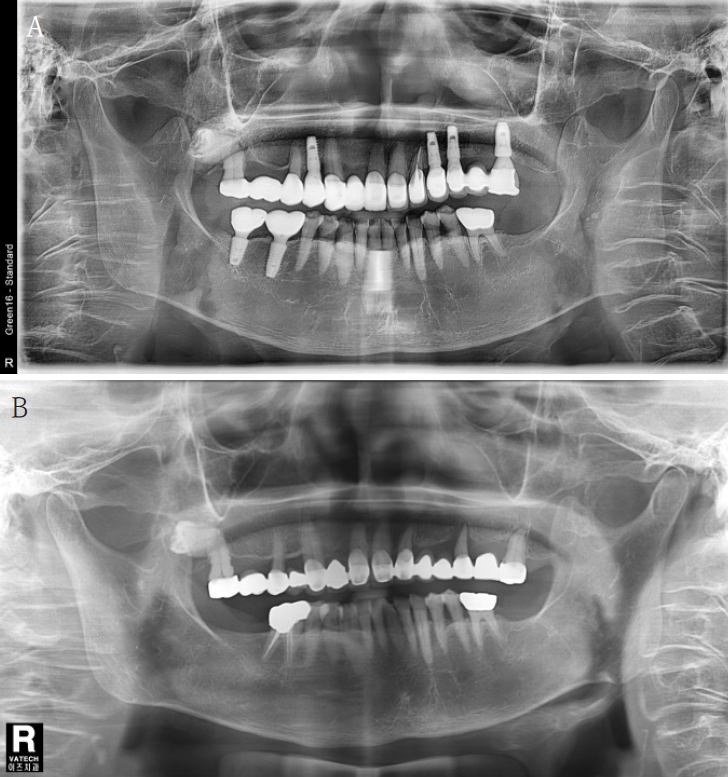

만 79세의 여환이 수개월 전부터 지속된 상악 우측 구치부 보철물의 동요 및 통증을 주소로 내원하였다. 임상 검사와 방사선 검사를 통하여 상악 우측 제2소구치와 제2대구치를 지대치로 하는 고정성 가공의치의 동요 및 동 부위 치주조직의 염증 상태를 관찰하였다(Fig. 1A). 고혈압약과 아스피린 복용 등의 의과 병력을 확인하였다.

A. A panoramic radiograph at the last visit. Vertical absorption of alveolar bone around the maxillary second molar on the right side is observed, and bone resorption progressed to the root of the tooth can be confirmed. B. First visit panoramic radiograph (12 years ago). The root of the second molar and the third molar on the right side of the maxilla are close to each other, and the third molar is impacted horizontally.

환자는 12년 전 동 치과에 상악 좌측 구치부의 통증을 주소로 처음 내원하여, 해당 부위의 발치를 시행하고 치과용 임플란트 시술을 시행하였다. 12년 전 내원 시 촬영한 파노라마방사선영상에서 상악 우측 제2대구치 부위의 수평적 골흡수가 관찰되었고 상악은 전체 치아가 수복된 상태였다. 상악 우측 제3대구치는 매복되었으며 상악 제2대구치와 근접하였다(Fig. 1B).

이번 내원 시 촬영한 파노라마방사선사진에서 우측 상악 제2대구치의 치근단 주위까지 진행된 수직 골결손이 관찰되어 동 치아의 발치를 계획하였다(Fig. 1A). 12년 전 초진 방사선영상과 마찬가지로 제3대구치가 근접하였고 그 위치가 움직이지 않았으므로 두 치아 관계의 자세한 분석을 위하여 CBCT(PHT-65LHS, Vatech, Hwaseong, Korea)를 촬영하였다(Fig. 2). CBCT는 94kVp, 8mA, 536x536x300pixels의 조건에서 촬영하여 FOV 161x90mm의 영상을 획득하였다. CBCT 영상에서 제2대구치와 제3대구치의 근접한 치근 부위는 주변 상아질보다 약간 낮은 방사선 흑화도를 보이는 부위가 관찰되었고 치근은 구근상을 보여 과백악질증의 소견을 확인할 수 있었으며, 그 부위의 백악질이 유합된 것으로 판단하여 유합으로 잠정 진단하였다.